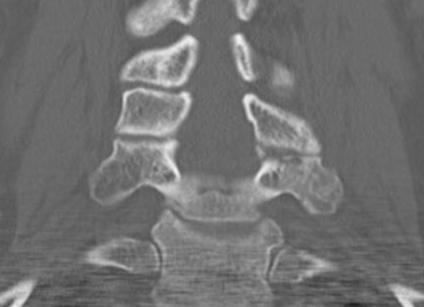

< 40% of the lateral mass

Superior articular facet fracture approximately 50% of the lateral mass